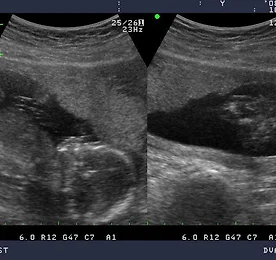

세 번째 검진, GA 10w+3 오늘 오후 5시, 세 번째 검진을 받으러 산부인과에 갔다. 그러고보니, 두 번째 검진에 대한 포스트는 하지 않았다. 두 번째 검진도 다 좋았다. 우리 한라도 잘 크고 있었고, 색시가 입덧으로 고생 하는 걸 빼면 모든 것은 순조로왔다. 측정한 CRL 상에서 10주 3일이 나왔다. 한라산의 정기를 받아 지난 8월 초중순 경 한라의 생명이 시작되었으니 딱 알맞은 수치다. 검진을 마치고 나와 부모님께 전화 드려서 길이가 무려 4cm에 육박하고, 팔다리도 다 보인다고 말씀드렸더니 아주 좋아하셨다. :) 마침, 일이 있어 부모님댁에 간 김에 초음파사진 꺼내서 한라가 이만큼 컸다고 보여드렸다. :) 지난 두 번째 검진에서 봤던 초음파에는 팔다리가 뚜렷하지는 않고 팔다리싹 정도만 보였는데, 이번에는 팔다리가 다 보이는.. 더보기